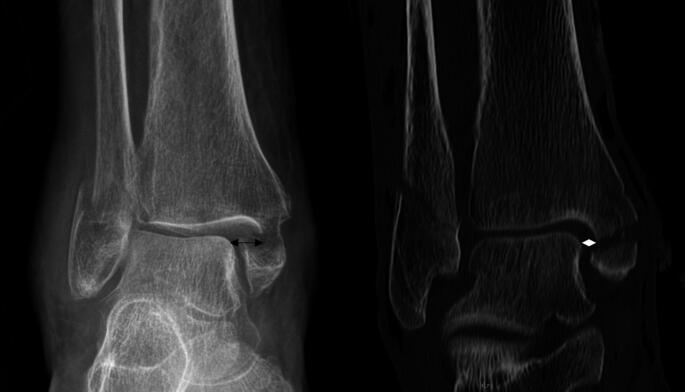

Purpose: Ankle fractures represent about 10% of all adult fractures, with increasing incidence. Dislocated ankle fractures often require delayed open reduction and internal fixation due to swelling, necessitating temporary stabilization using a cast or an external fixator. This study aims to assess risk factors for insufficient preliminary reduction immobilized by a cast, focusing on medial clearspace and posterior malleolus fragment size, to identify fractures that would benefit from initial stabilization with an external fixator.

Results: 134 patients met the inclusion criteria. The most common fracture type was AO 44B3, with 71.6%. Sufficient reduction was achieved in 53.7% of patients. Multiple regression analyses revealed the initial medial clearspace at the time of dislocation as an independent risk factor for insufficient reduction after reduction. ROC-analysis revealed that a initial medial clearspace at the time of dislocation of 9 mm is a predictor for insufficient reduction with a sensitivity of 88% and a specificity of 55%.

Conclusion: Initial medial clearspace was an important predictor for insufficient reduction in a cast, with 9 mm being identified as the cutoff for critical initial medial clearspace. Therefore, we recommend primary external fixation or acute internal fixation, if the soft tissue allows it for those patients with initial medial clearspace of > 9 mm. This approach may prevent secondary dislocation, reduce swelling, and expedite definitive surgery.